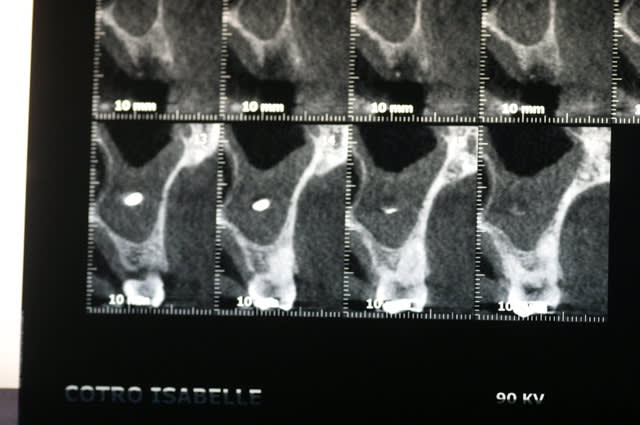

patiente, 50 ans, non fumeuse, la 25 a été extraite car fracturée.

L'idée était de poser un implant pour remplacer cette 25.

Je me serais bien lancé pour un premier sinus lift, mais l'épaississement de la muqueuse et le bout de pâte d'obturation me laisse perplexe.

ps :je n'ai pas de pano.